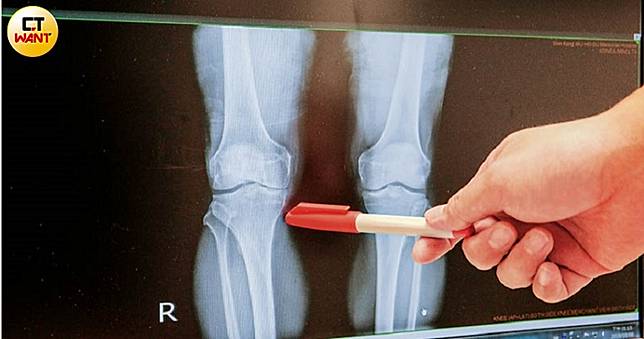

退化性關節炎初期好發於膝蓋內側,骨頭間隙會明顯狹小。左為關節退化、右為正常關節。(圖/鄭清元攝)